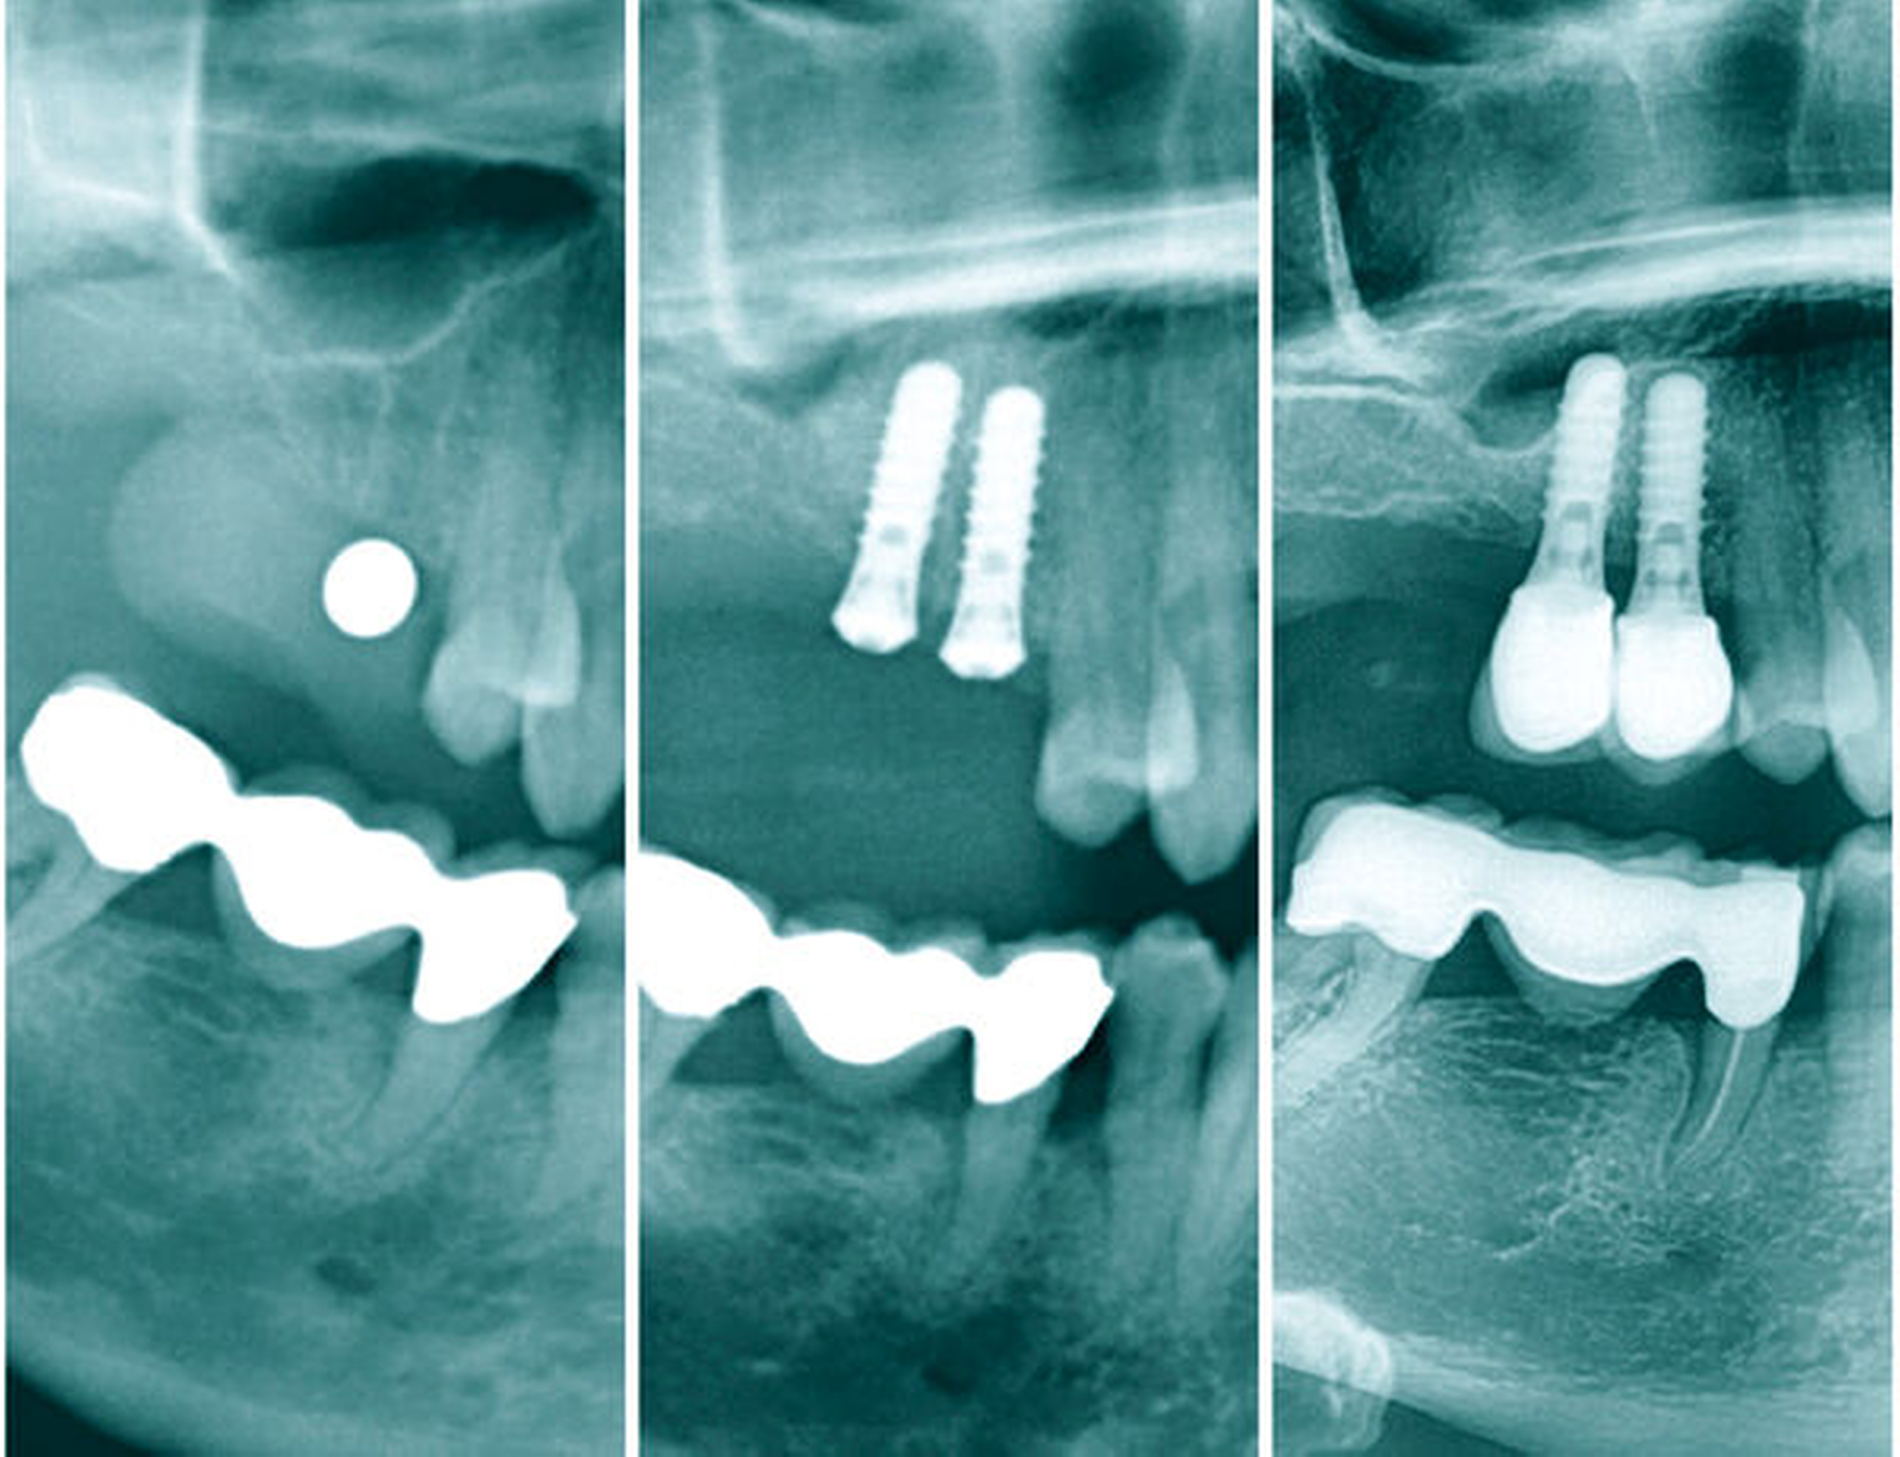

Die anamnestisch unauffällige 56-jährige Patientin erschien auf Überweisung ihres Hauszahnarztes mit dem Wunsch nach festsitzendem Zahnersatz zur Beratung in unserer Praxis. Die Patientin hatte schon vor einigen Jahren mehrere Implantationen in unserer Klinik durchführen lassen und lehnte einen herausnehmbaren Zahnersatz ab. Bei der intraoralen Befundaufnahme zeigte sich ein konservativ und prothetisch suffizient versorgtes Gebiss sowie eine Freiendsituation im zweiten Quadranten mit fehlenden Zähnen Regio 25–28 und eine Schaltlücke in Regio 36. Röntgenologisch konnte im Orthopantomogramm in Regio 25 und 26 eine Restknochenhöhe von 2,5 bis 3 mm festgestellt werden, wodurch ein externer Sinuslift nötig wurde, um die gewünschte Implantatversorgung zu realisieren. Nach ausführlicher Aufwands-, Kosten- und Risikoaufklärung stimmte die Patientin der Behandlung zu.

In den Abbildungen 6 bis 9 sind mehrere Fälle mit langem Beobachtungszeitraum dargestellt. Beachtenswert ist vor allem der zu beobachtende vollständige Umbau des Knochens inklusive der Ausbildung einer neuen Kompakta. Die augmentierten Bereiche sind nach wenigen Jahren nicht mehr als solche zu erkennen. Die Arbeit mit autologem Knochen ist insbesondere für die Patientengruppe interessant, die bevorzugt nach biologisch sicher verträglichen Behandlungen sucht. Dieser Trend nimmt unseren Beobachtungen nach stetig zu. n